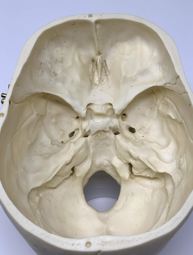

Skull landmarks

uThe base of the skull is rough, with many bony protuberances

uThese ridges can result in injury to the temporal and frontal lobes of the brain during rapid deceleration

udefinition: when the head slows or stops suddenly and the brain continues to move